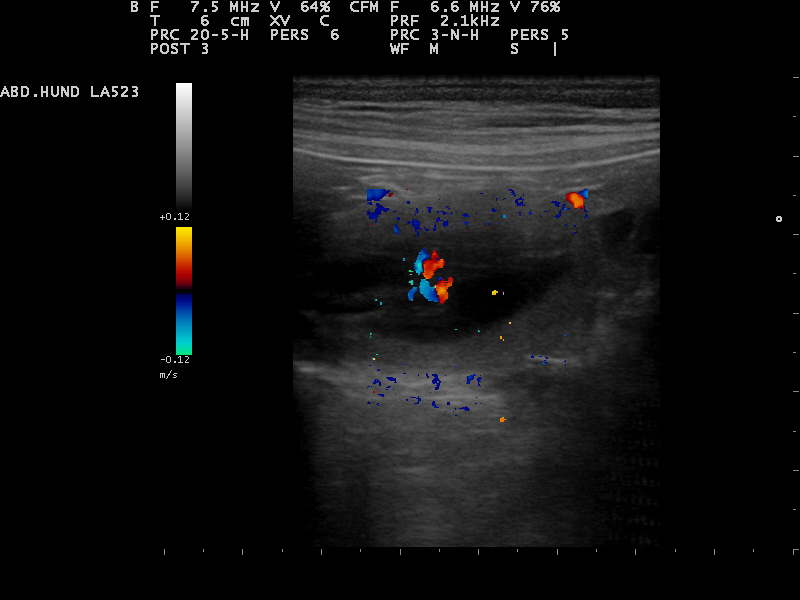

Am 22. Tag sind die Embryonen sichtbar. Der Herzschlag kann zur Diagnose der Trächtigkeit herangezogen werden. Anstrengende Aktivitäten sind

15.12.2015 jetzt zu vermeiden.Die Proteinzufuhr im Futter kann erhöht werden. Hierfür eignet sich sehr gut die Gabe von Welpenfutter. Zu diesem Zeitpunkt kann

mit einer Ultraschalluntersuchung der Zustand der Trächtigkeit festgestellt werden. Besprechen Sie mögliche Risiken einer solchen Untersuchung mit dem Tierarzt.

22.12.2015 Dies ist der beste Zeitpunkt, um die Trächtigkeit anhand des Herzschlags zu diagnostizieren.

Die Embroynen sind etwas walnussgroß und sind gleichmäßig im Uterus verteilt.

Die Ultraschall-Untersuchung hat ergeben das Alexa trächtig ist und wir gespannt auf

unseren B-Wurf warten können

Das sind die ersten Bilder unseres B-Wurfes